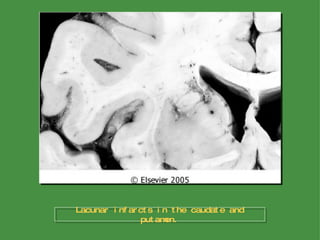

Hypertensive Cerebrovascular Disease Lacunar Infarcts Hypertension affects the deep penetrating arteries and arterioles that supply the basal ganglia and hemispheric white matter as well as the brainstem An important clinical and pathologic outcome of CNS arterial lesions is the development of single or multiple, small, cavitary infarcts --  lacunes , or lacunar state ( etat lacunaire ) These are lakelike spaces, less than 15 mm wide, which occur in the lenticular nucleus, thalamus, internal capsule, deep white matter, caudaste nucleus, and pons

Lacunar infarcts in the caudate and putamen.